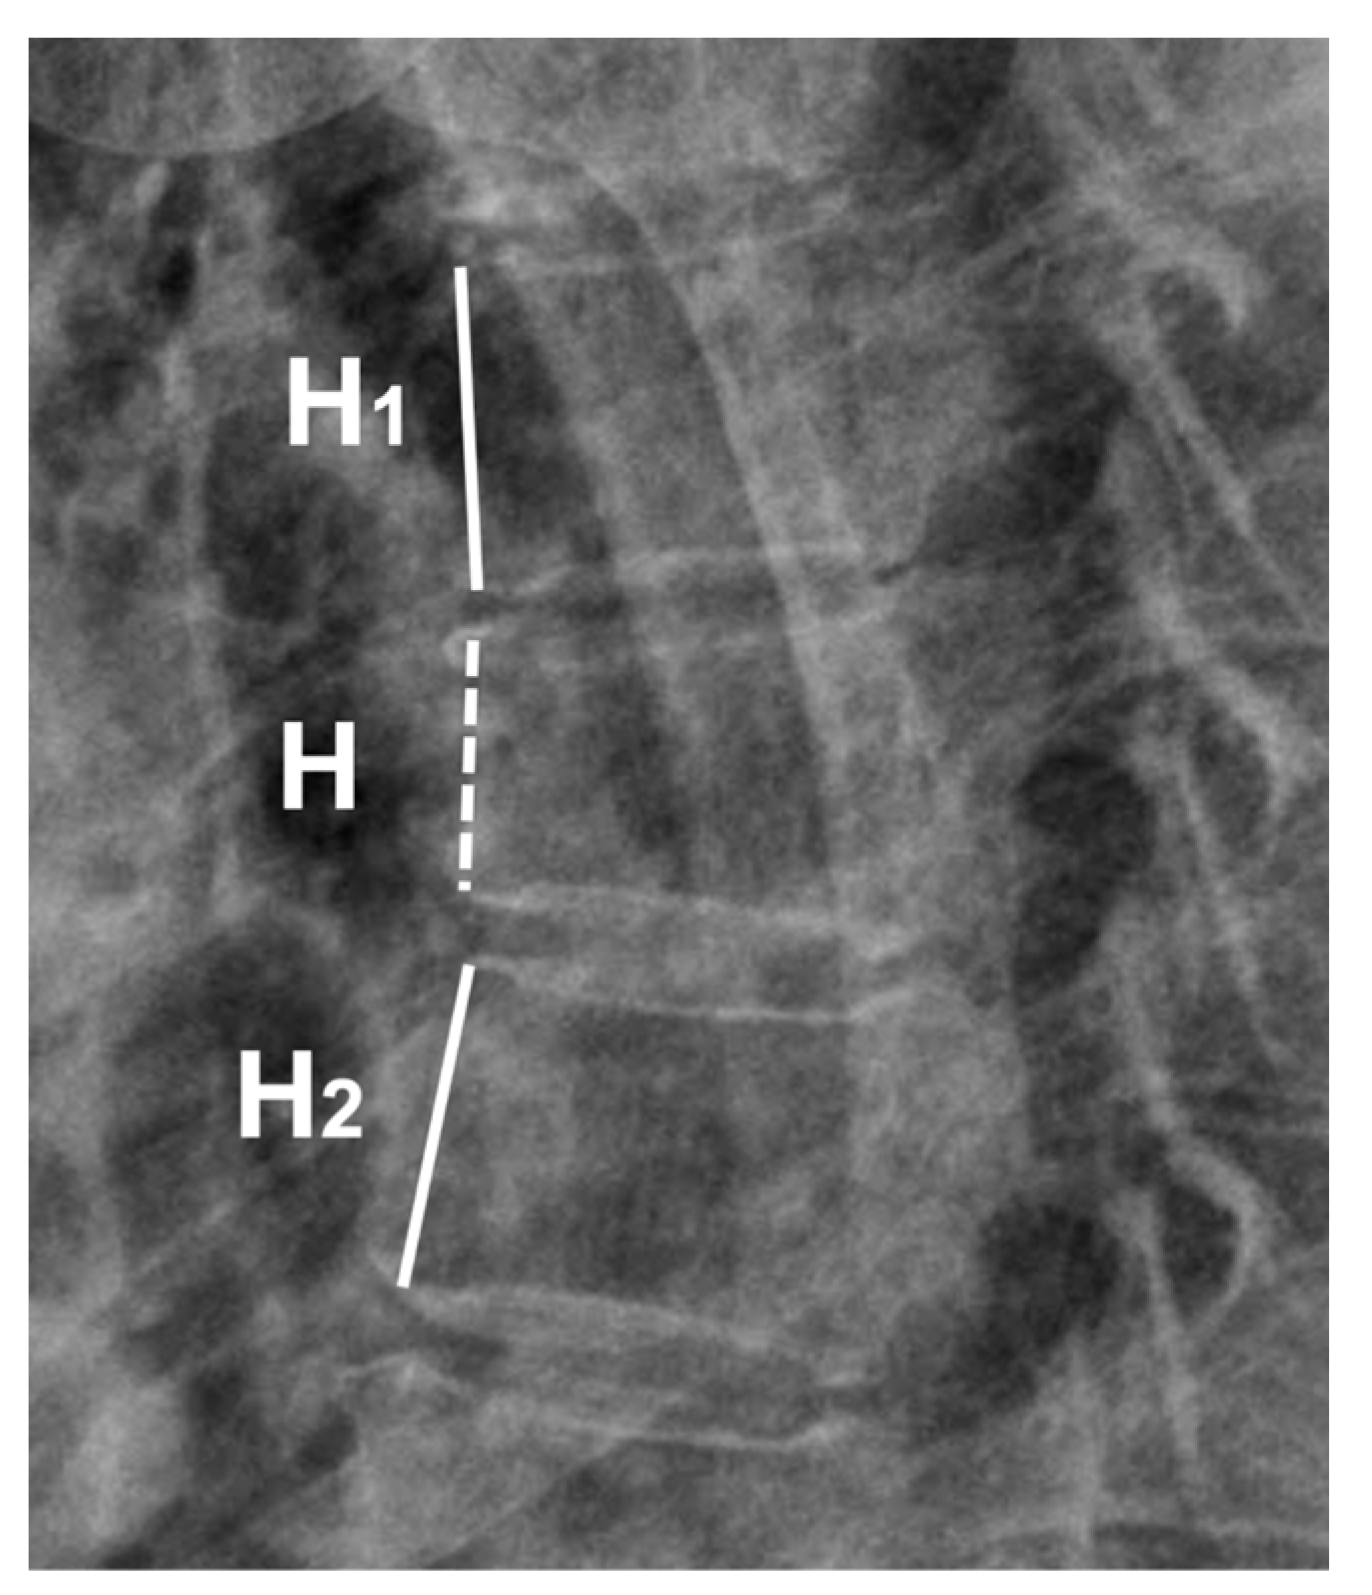

2.1. Data Collection and Radiographic Measurement: Anterior Body Compression Percentage